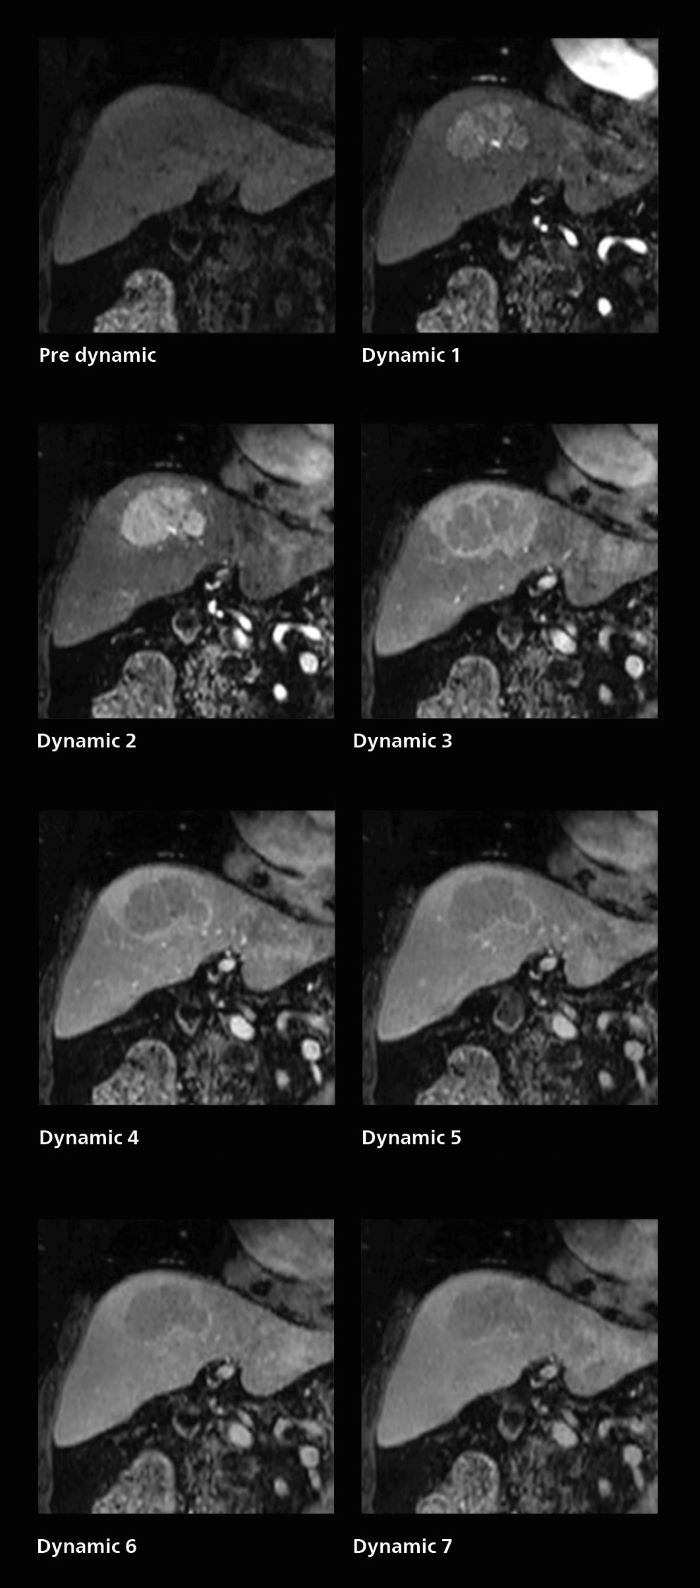

Dynamic MRI of liver using SmartSpeed

A patient was referred for MR imaging of HCC. A double arterial volume dynamic study was performed. Since it is a volume dynamic study, it can also be evaluated using MPR images. Performed on Elition X.

Fast dynamic liver MRI: volume dynamic study of 1.05 min, 1.6 x 1.8 x 2.0 mm, 200 slices

The hospital’s routine ExamCard for dynamic MRI of the liver uses total scan duration 1:05 min, dynamic scan time 9.2 sec, 1.6 x 1.8 x 2.0 mm, 200 slices, acceleration factor 8.

Also in dynamic MRI of the liver Dr. Katahira sees important improvements. While previously his scan used 9 seconds for a 5 mm slice, SmartSpeed now allows him to achieve a thin slice volume scan (1.6 x 2.1 x 2mm) with double arterial phase using acceleration factor 8. He indicates this is very useful for the radiologist when diagnosing, especially because it can provide a high temporal resolution.